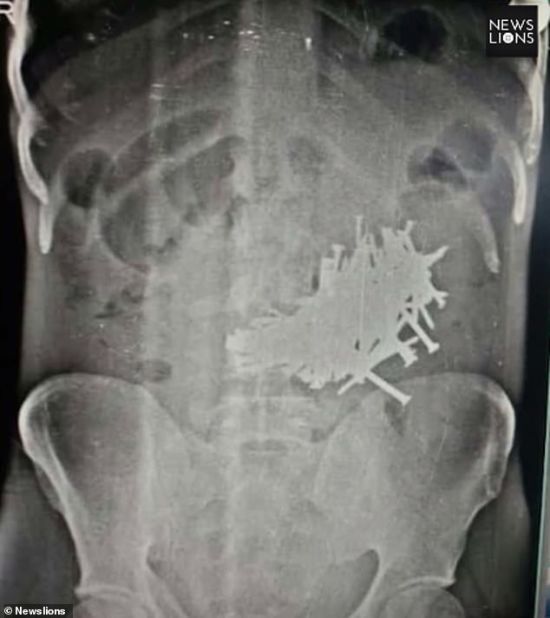

В Литве хирурги удалили из желудка мужчины более килограмма гвоздей и шурупов. Об этом сообщила пресс-служба Клайпедской университетской больницы. Мужчина был госпитализирован с жалобами на боль в животе. inforesist.org »

По словам врачей, мужчина начал глотать металлические предметы месяц назад после отказа от алкоголя. unian.net »

В госпитале Клайпедского университета Литвы хирург удалил из желудка мужчины почти килограмм железа в частности гвозди длиной до 10 сантиметров. Мужчина глотал их в течение месяца после того, как бросил пить алкоголь. glavnoe.ua »

Некоторые объекты имели длину 10 сантиметров comments.ua »

В Литве врачи Клайпедской университетской больницы удалили из желудка мужчины более килограмма гвоздей, шурупов и гаек news.liga.net »

Гвозди достигали пяти сантиметров в длину. ru.tsn.ua »